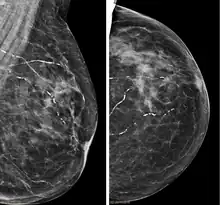

| Right breast mammograms showing several calcified arterioles. Patient 94 years old. | |